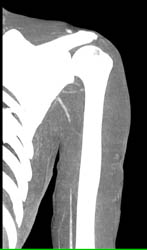

Subclavian Artery Thrombosis